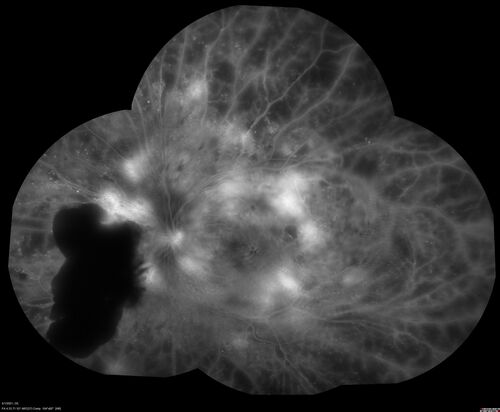

Pregnant - 25 weeks - new onset PDR and DME both eyes - Treated with PRP and ozurdex

29 year old female.  Patient is 25 weeks pregnant and having flare up of retinopathy in both eyes. She states it is worse in the left. Patient has trouble with distant vision.  At most recent visit, 1 years ago, VA was 20/20 OU.  Two years ago anterior uveitis x 1 episode with normal labs (HLAB27, FTA, ACE, Lyme).  2017-2020 – Lucentis for DME left eye only.

PMHx: Type I DM since teenager, hyperlipidemia

BP was normal